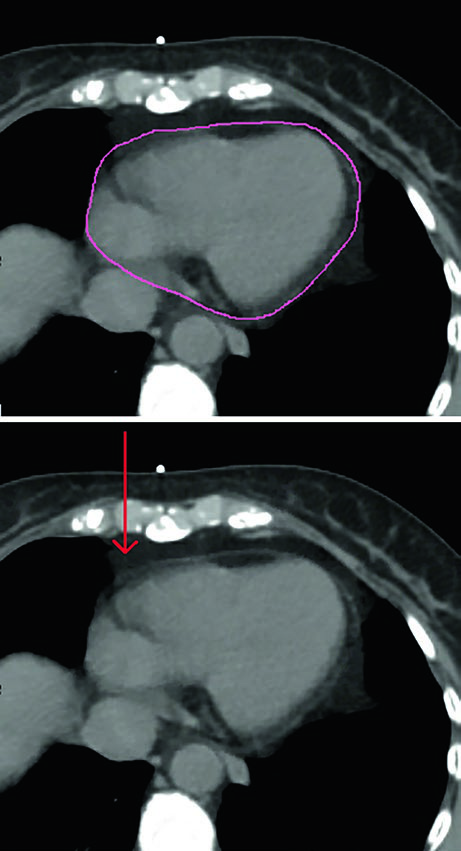

Coração, pulmões e os detalhes do contorno cardíaco

Em todos os casos, os órgãos de risco devem incluir coração e pulmões. O capítulo especifica que o coração deve ser contornado superiormente até a bifurcação da artéria pulmonar, incluindo o pericárdio e a gordura epicárdica situada entre o músculo cardíaco e o pericárdio. A gordura pericárdica que fica fora do pericárdio não precisa ser incluída. A figura correspondente mostra exatamente essa diferença e evita uma fonte frequente de inconsistência entre planejadores.

Os autores também organizam a hierarquia do que medir. A melhor evidência para proteção cardíaca continua sendo a redução da dose média no coração. Ao mesmo tempo, eles registram que estão surgindo dados que sugerem relevância para a dose recebida pela artéria descendente anterior esquerda e pelo ventrículo esquerdo. Por isso, essas estruturas podem ser contornadas com base nos atlas publicados por Feng et al. e Duane et al., exatamente como indicado nas referências do capítulo.

Essa combinação entre um desfecho consolidado, que é a dose média cardíaca, e uma avaliação mais refinada de LAD e ventrículo esquerdo ajuda a ler o texto sem exageros. O capítulo não troca um parâmetro robusto por outro ainda emergente. Ele propõe que a equipe some precisão quando isso fizer sentido, sem abandonar o indicador com melhor suporte de evidência. Em prática diária, esse equilíbrio combina bem com a recomendação de considerar DIBH nos casos à esquerda e com o uso de pequenos bloqueios por MLC quando o plano supino exigir proteção cardíaca adicional.